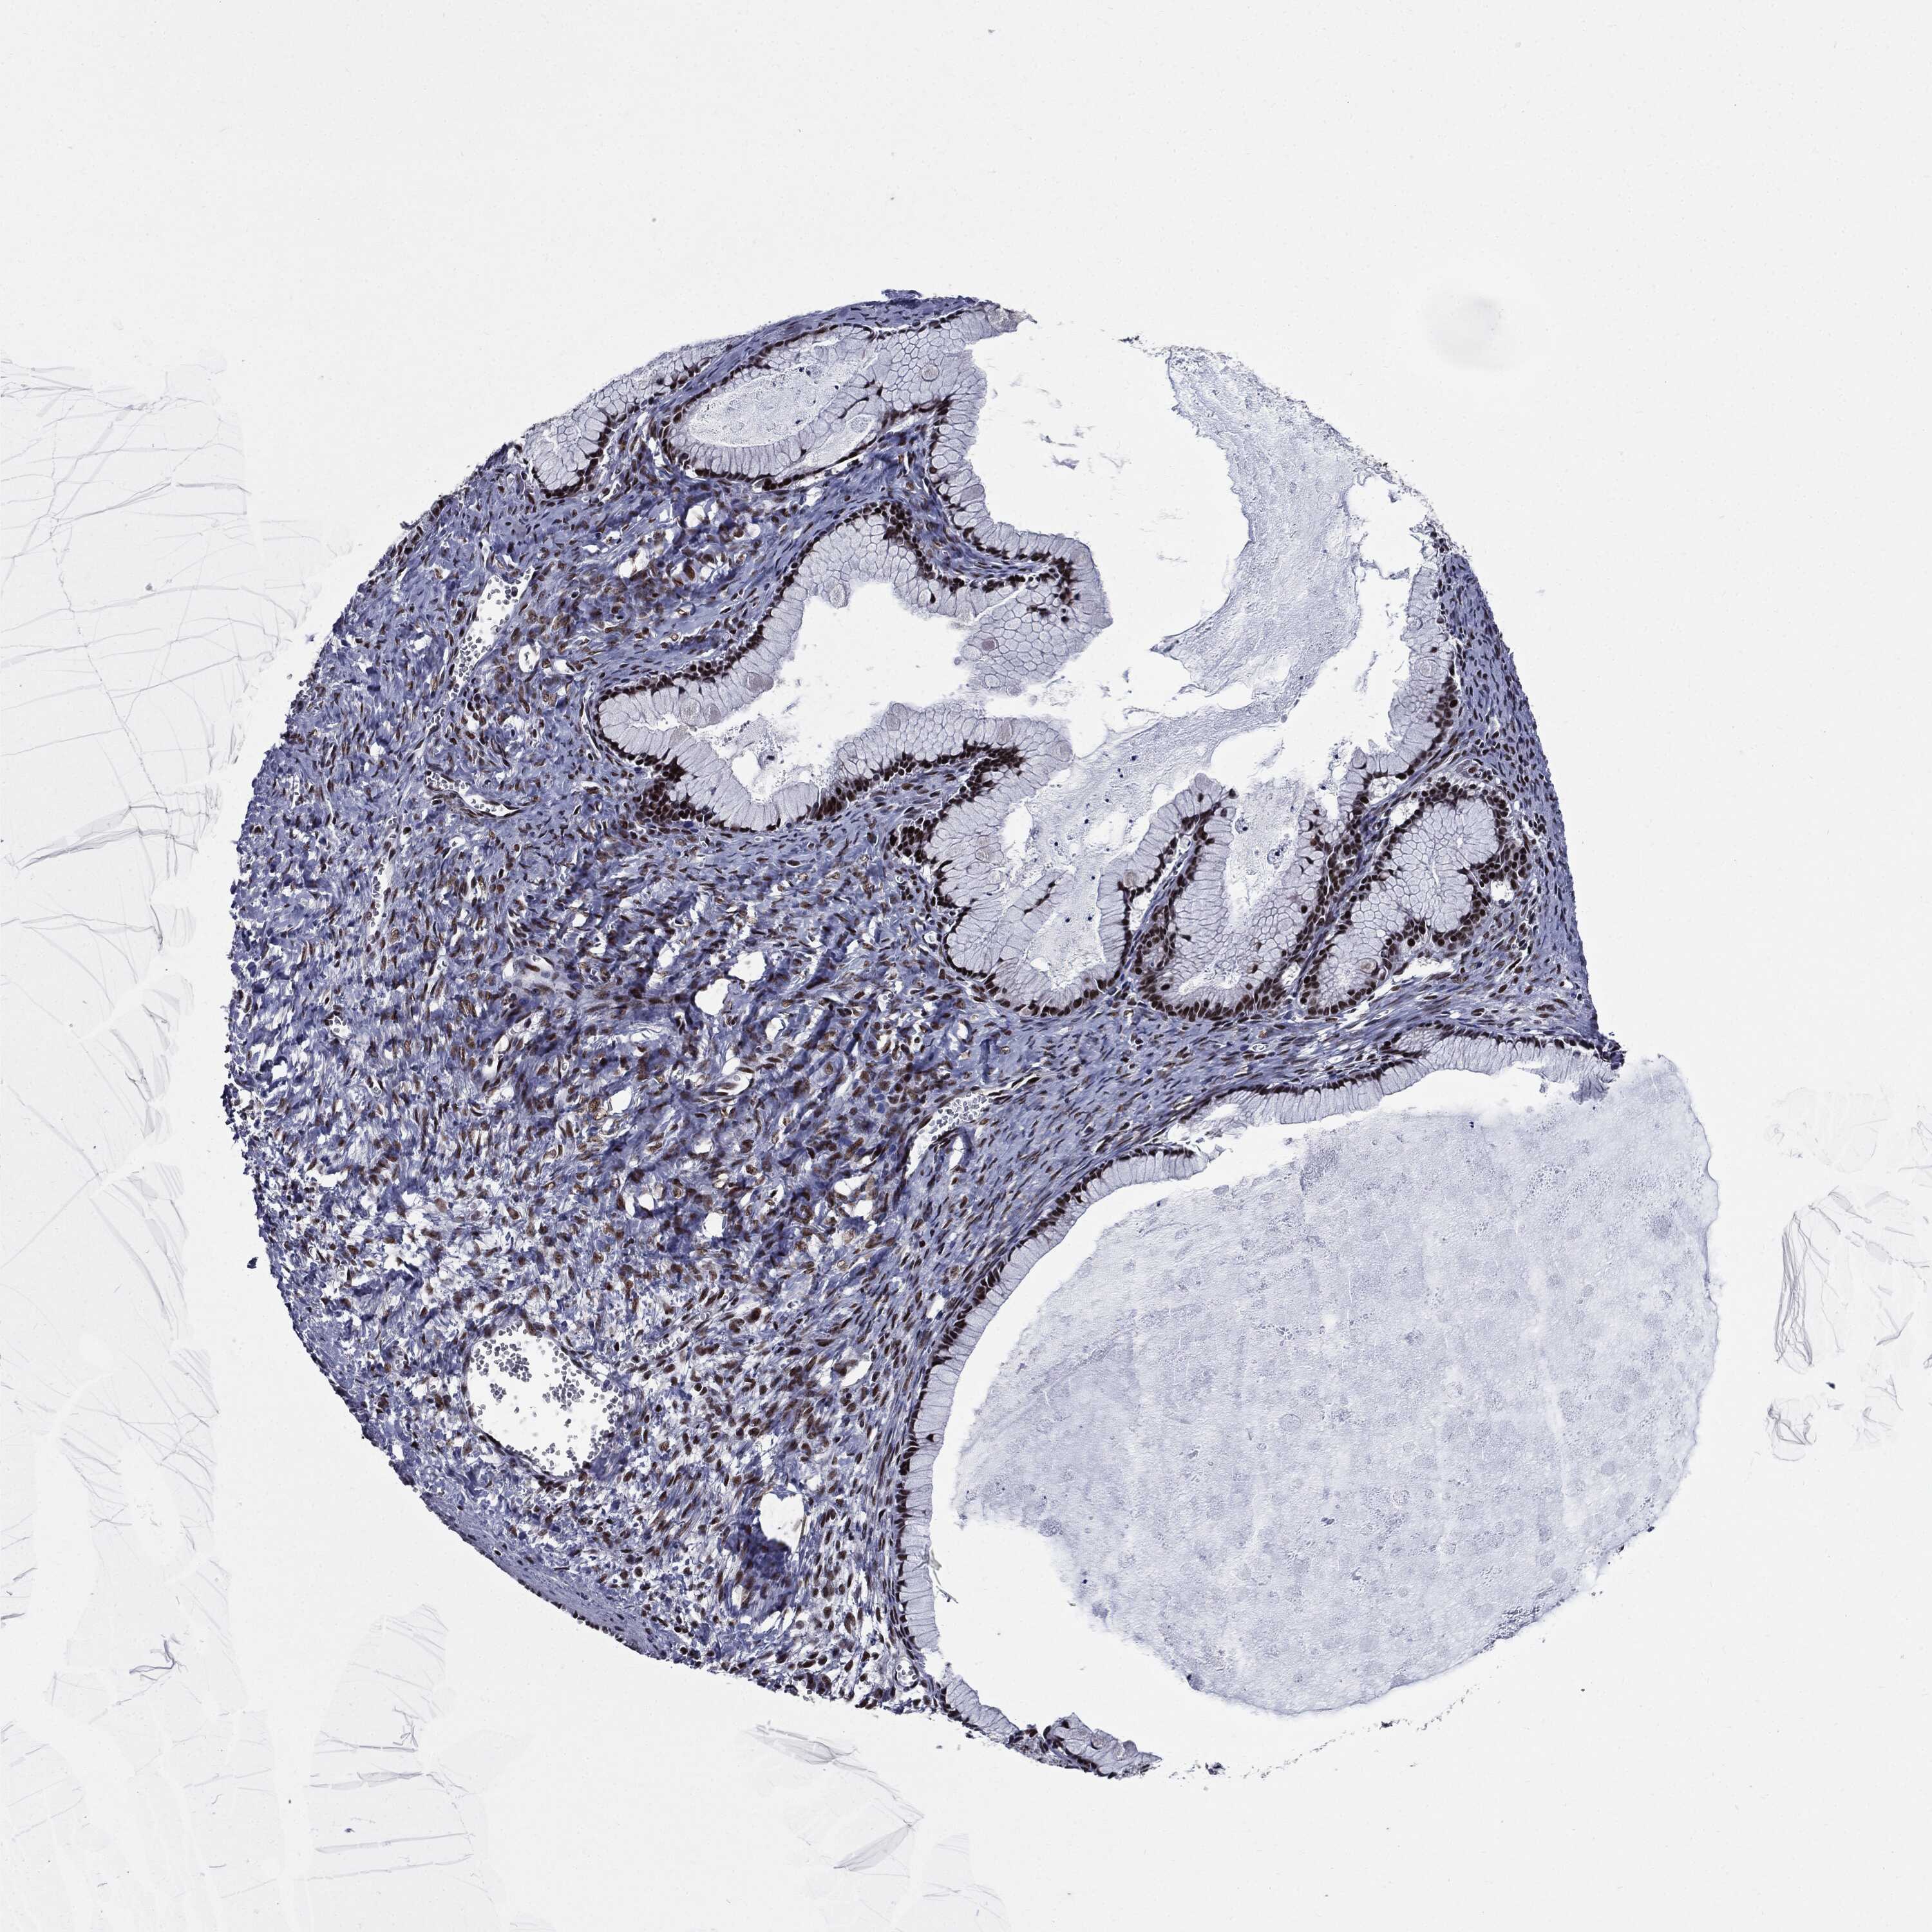

Antibody CAB025417

Staining

High

Medium

Low

Not detected

Intensity

Strong

Moderate

Weak

Negative

Quantity

>75%

75%-25%

<25%

None

Location

Nuclear

Cytoplasmic/membranous

Cytoplasmic/membranous,nuclear

Cystadenocarcinoma, serous, NOS

Carcinoma, endometroid

Cystadenocarcinoma, mucinous, NOS

Carcinoma, NOS